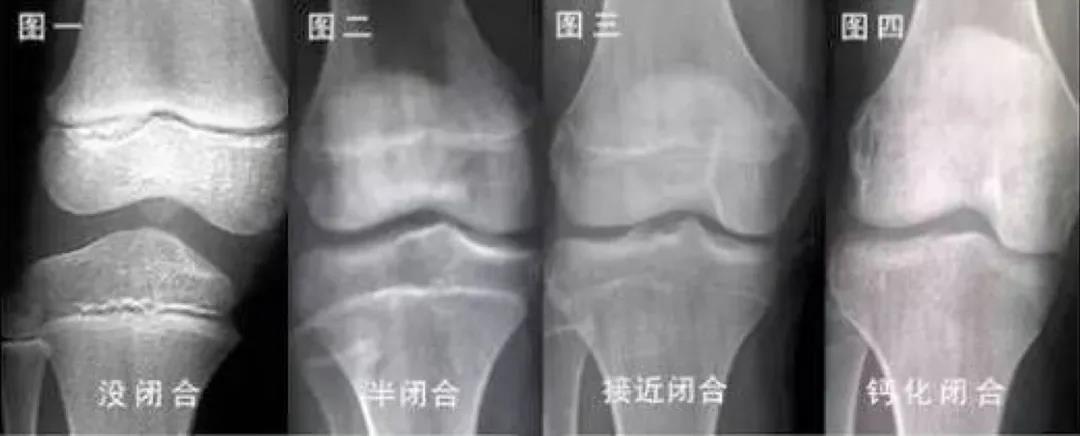

生长板存在固有的程序性变化,随着时间的推移,生长板出现功能性和组织性的衰老变化,软骨细胞不再具有增殖、骨化的能力,此时生长板就会闭合,也就是我们经常听到的“骨骺线闭合”,身高便不再增长。

骨龄与生长板结构性变化存在密切的关系,骨龄小代表着生长空间足、还能长得更高,骨龄大说明生长空间小、身高增长的时间少。